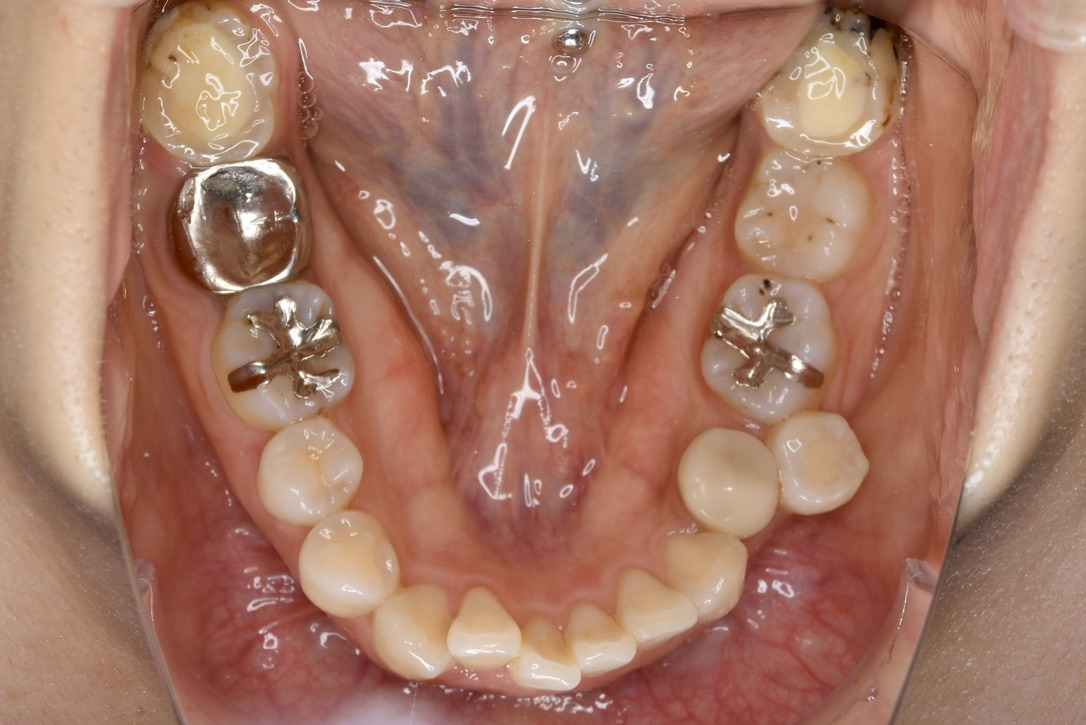

BEFORE

診断名・主な症状 叢生を伴う上顎前突

治療内容 上下とも歯を2本抜いて、上の前歯を後方に引きながら、でこぼこを治しました。

抜歯部位 上 両側4番目

下 右側4番目、左側5番目